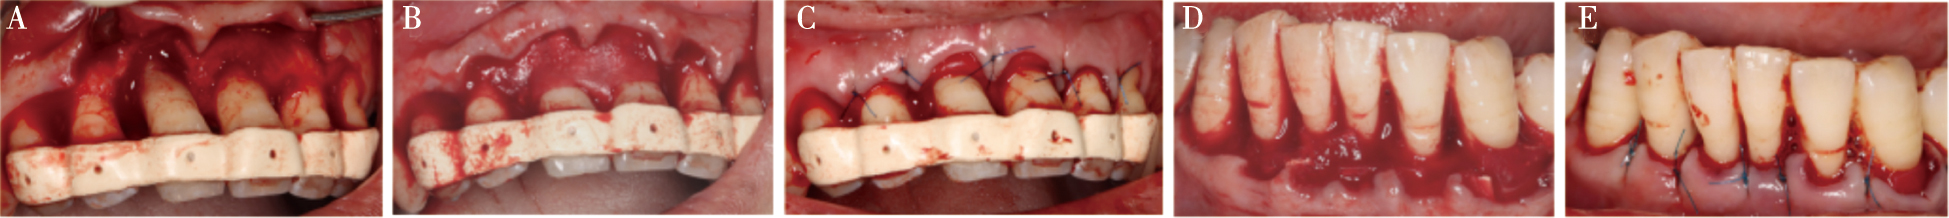

Zhang CR, Liu Q, Yang JW, et al. A digital technique for splinting periodontally compromised mobile teeth in the mandibular anterior region[J]. J Prosthet Dent, 2021, 125(4): 560-563.

Liu YC, Bai SZ, Zhong S, et al. Digital workflow for periodontal splinting with a guided device[J]. J Esthet Restor Dent, 2023, 35(4): 621-624.